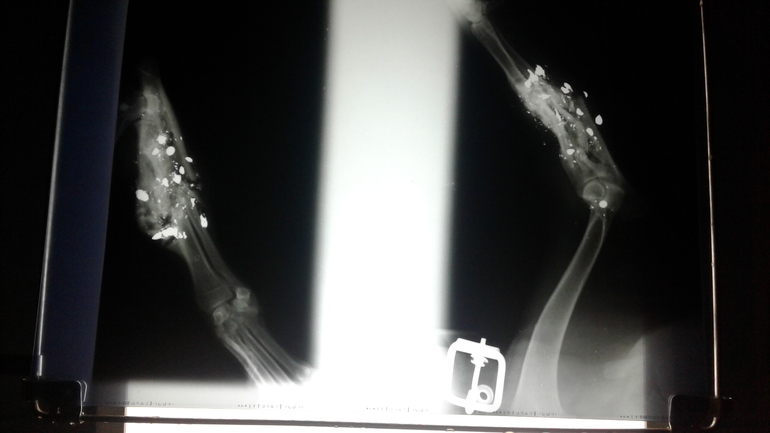

Рентгеновские снимки лапки мамочки( белые круглые "зерна" это то ли разорвавшаяся бомба с металлическим наполнением, или пули от травматики, сейчас уже не установишь((( а так же множественные сросшиеся переломы.

Когда мы взяли малышек с улицы, мы думали, что у мамочки перелом и мы сможем его прооперировать, но оказалось что у нее локоть нашпигован металлическими осколками и весь переломан, а так как травма произошла давно, уже образовался костный мозоль.

Она немножко прихрамывает, но это совершенно ей не мешает и несмотря на то, что малышка пострадала от рук людей, она осталась такой же игрулькой, как маленький щеночек, беззаветно доверяющей и любящей людей. Так же она воспитала и дочек)